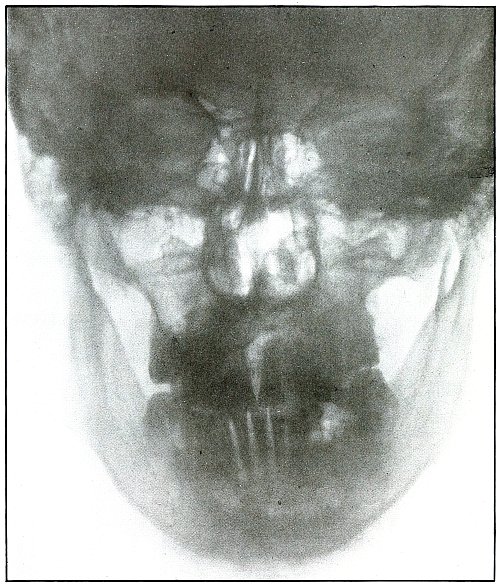

Plate 2.

[Pg 15]

Rifle—Plate 2.

HEAD.

Gunshot Wound of the Head, with Lodgment of the Missile.

Wound of entrance, near outer canthus, with course through eyeball to

ethmoid body.

Wound of exit, none.

The Bulgarian Mannlicher bullet, shown half actual size on the plate,

must be inclined on its long axis, about 30° from the perpendicular,

to the plane of the plate.

The slight penetration of the missile and its normal character show

that, having struck no intervening object, it indicted the wound at

extreme range.

The treatment should meet the indication for removal of missiles in

all superficial or easily accessible locations and when they cause

reaction.

Results to be expected are favorable except for loss of the eye.

[Pg 16]

Plate 3.

[Pg 17]

Rifle—Plate 3.

HEAD.

Gunshot Fracture of the Ramus of the Lower Jaw.

Wound of entrance, in the cheek behind the angle of the mouth.

Wound of exit, below the tip of the mastoid.

The course of the bullet was almost tangential to the ramus of the

jaw, anteroposteriorly. The slight fragmentation, which is hardly

more than a splitting of the bone, with little or no displacement,

indicates that the wound was made by a rifle bullet at moderate

velocity and at mid or long range.

Treatment is expectant.

Results are favorable.

[Pg 18]

Plate 4.

[Pg 19]

Rifle—Plate 4.

HEAD.

Gunshot Fracture of the Ramus of the Lower Jaw.

Wound of entrance, over the anterior border of the right ramus.

Wound of exit, beneath the lobe of the ear.

The wound was made by a rifle bullet with the velocity of long range,

because wounds of a shrapnel ball never show such slight injury

without lodgment or without marks of lead.

The damage of the bone was very slight, as only a superficial fragment

was chipped off. There were no signs of primary infection. Reaction

and periostitis suggested the radiograph after infection had rarefied

the fragment, shown but very faintly on the left side of the plate.

The postero-anterior skull radiograph was made with the face

superimposed upon the photographic plate.

Treatment, incision and drainage.

Results, good.

[Pg 20]

Plate 5.

[Pg 21]

Rifle—Plate 5.

HEAD.

Gunshot Fracture of the Body of Lower Jaw,

with Great Fragmentation and Displacement.

Wound of entrance, to the left side of the median line of the lower

jaw below the alveolar process, with course ranging downward and

backward.

Wound of exit, with extensive laceration, beneath lower border of the

bone.

The wound was caused by a rifle bullet at high velocity at or less

than mid range. The fragments are many and rather small, so that much

bone was lost through the wound of exit. This effect was produced by

the splitting due to the relative friability of the bone and to the

imparting of the momentum of the missile to the detached fragments,

which, together with the missile, effected the considerable laceration

of the wound of exit.

Treatment, difficult; guided by septic conditions and surgical means

available.

Results in such cases are favorable to life but topically unsatisfactory.